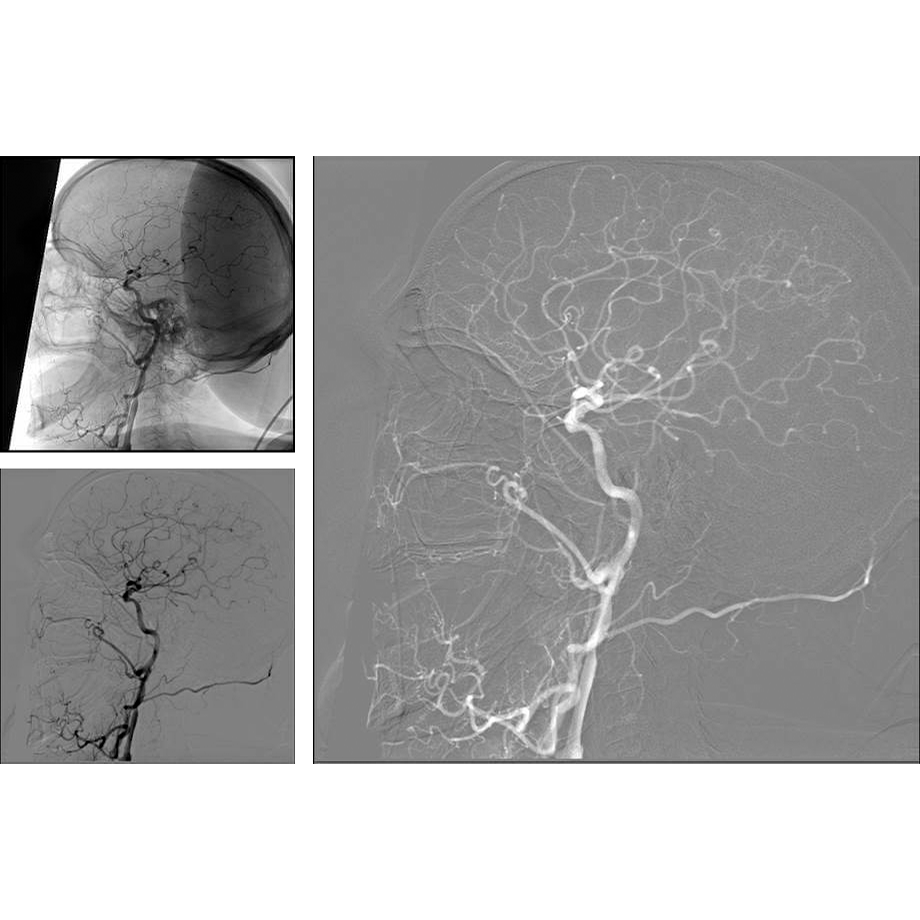

The Ziehm Vision RFD Hybrid Edition offers SmartVascular workflows tailored specifically to hybrid interventions for a seamless transition between fluoroscopy, digital subtraction angiography (DSA), and roadmapping (RSA). The open injector interface is supplemented by a CO₂ option, allowing patients with contrast agent intolerance to also be treated successfully.